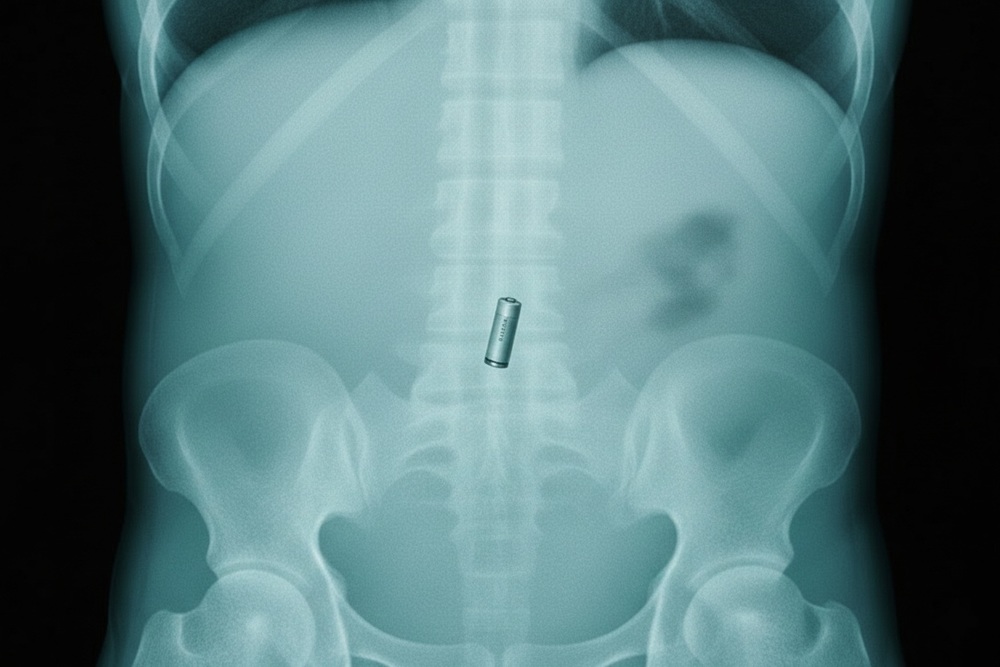

Работать врачам пришлось с мальчиками девяти и двух лет, которых доставили в стационар. Старшему эндоскописты оперативно извлекли крупный элемент питания прямо из желудка. В случае с двухлетним ребёнком ситуация осложнилась тем, что инородные тела уже опустились в кишечник. Врачи вместе с рентгенологами установили круглосуточное наблюдение и решили не оперировать малыша, рассчитывая на естественный выход предметов. Эта тактика оказалась верной, и батарейки покинули организм, не травмировав органы.